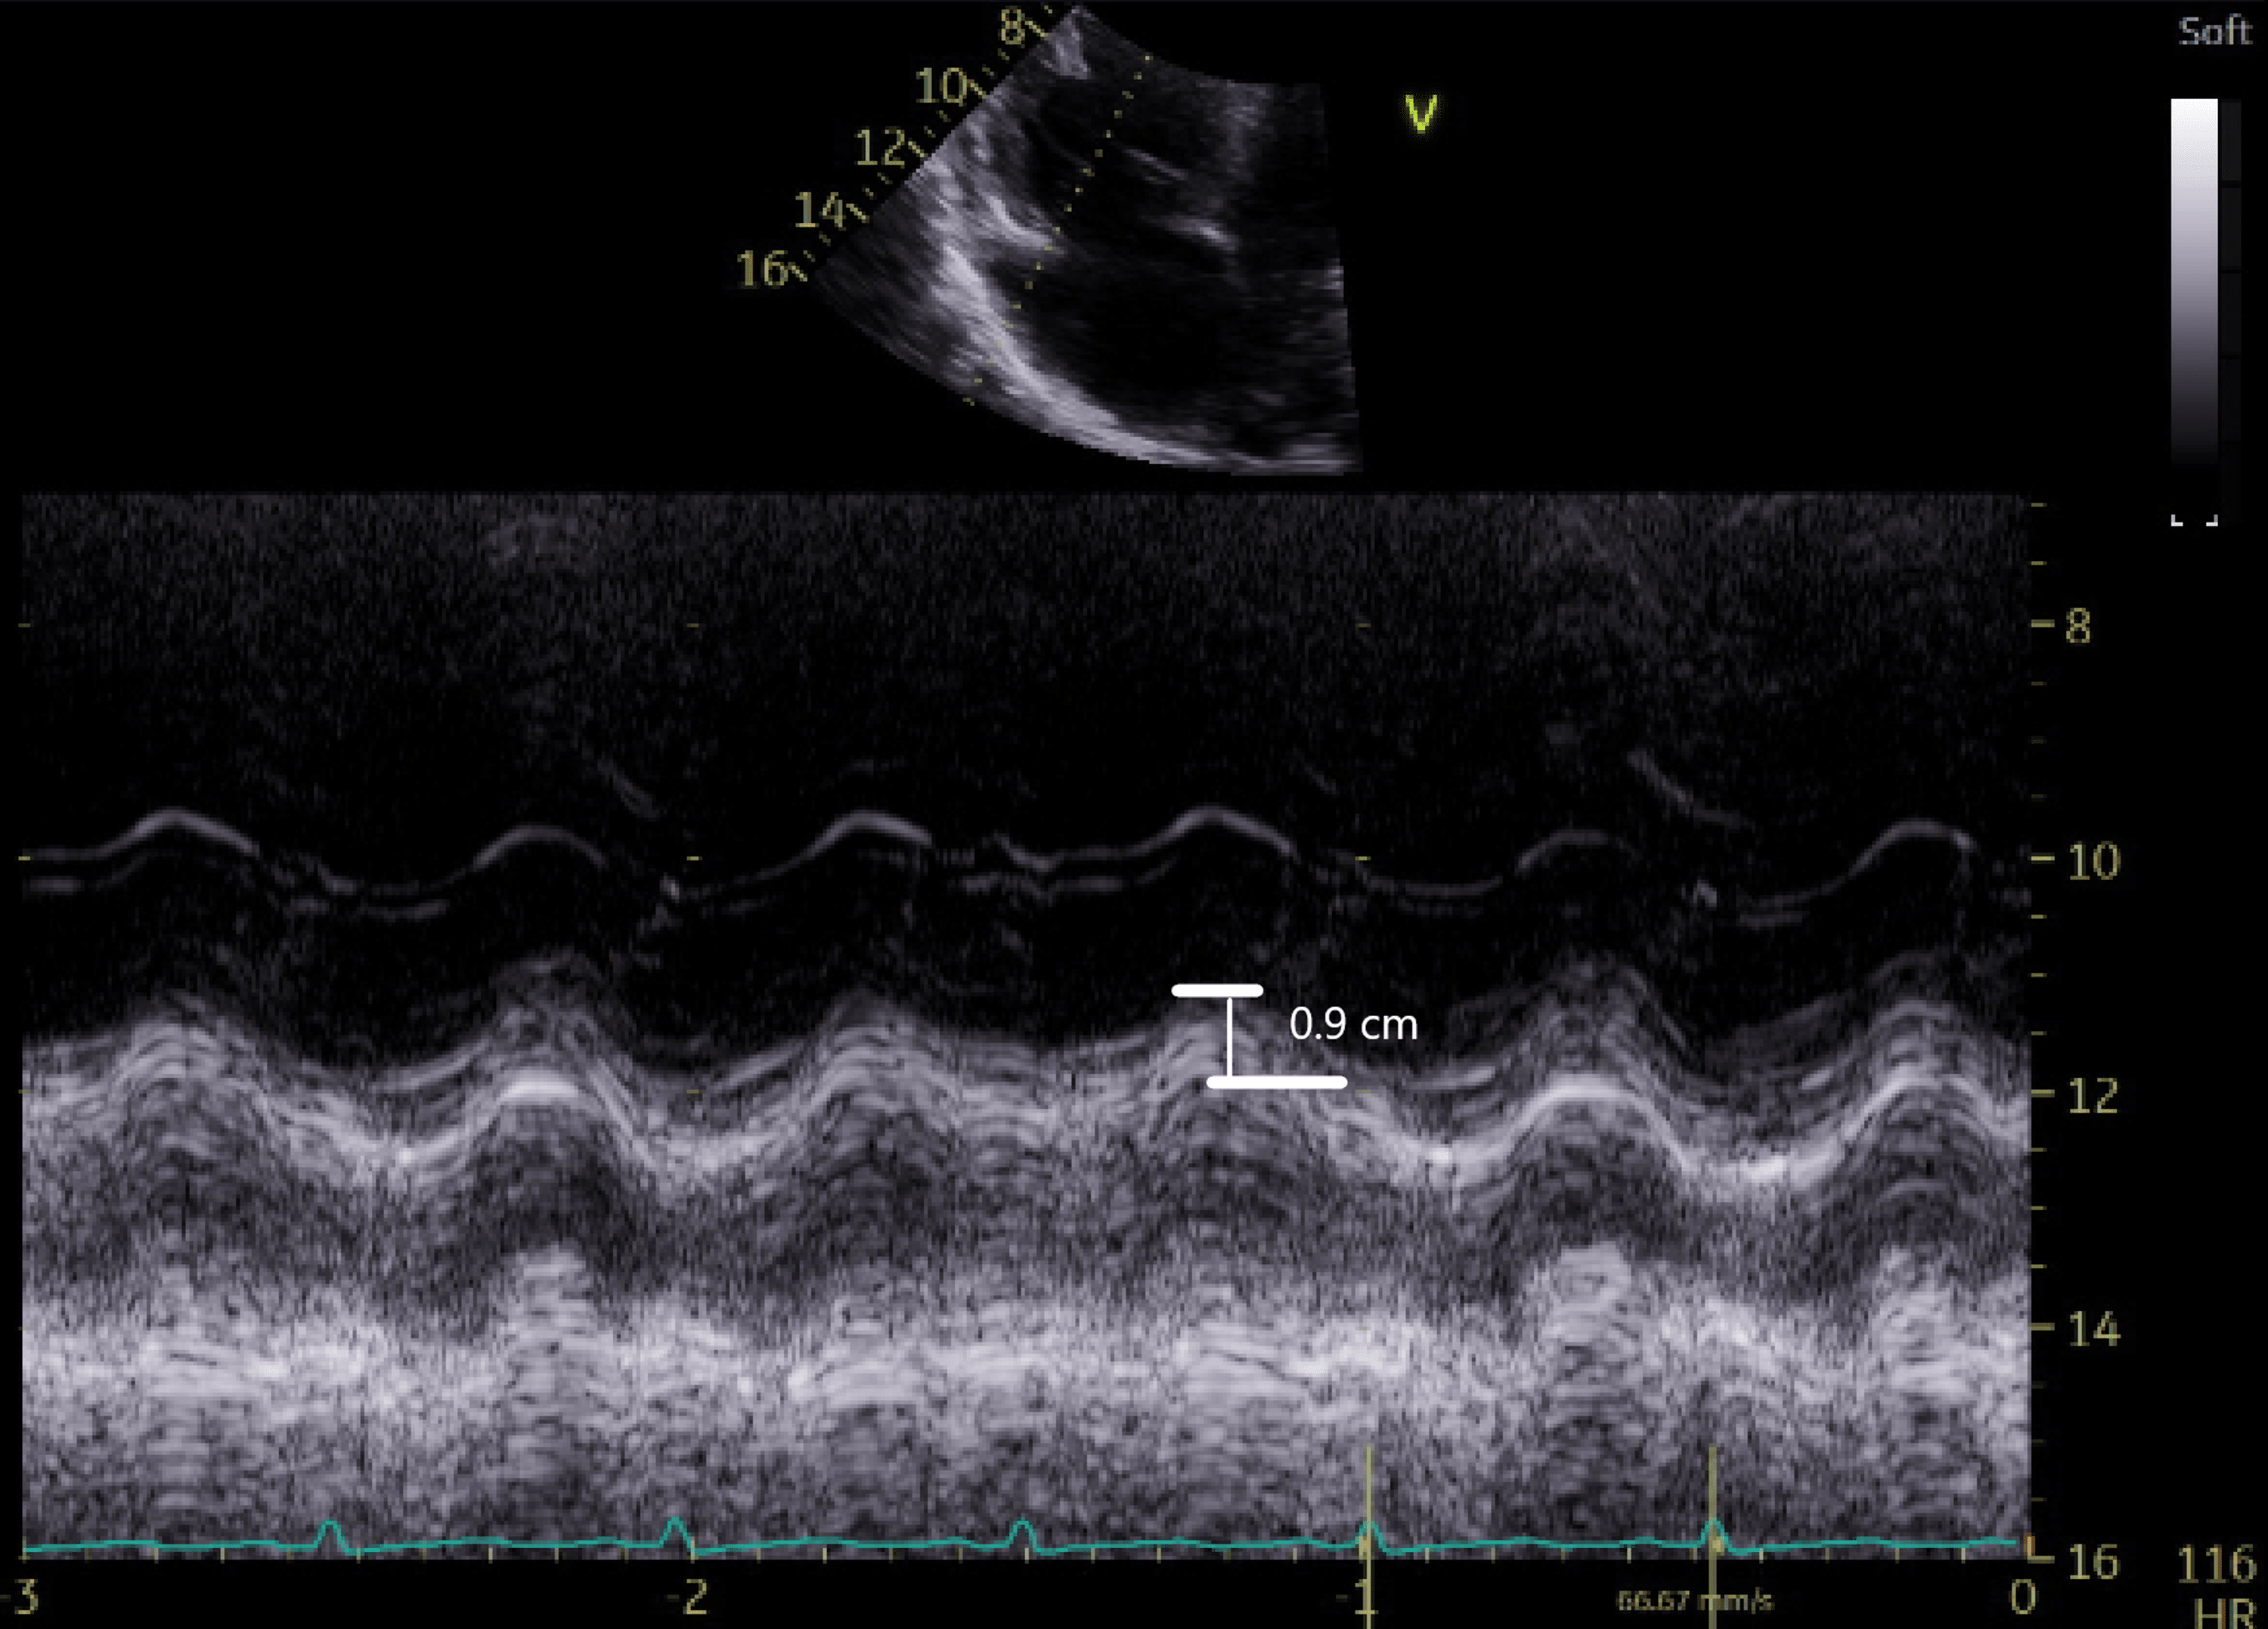

Low TAPSE assessed by Mmode transthoracic echocardiography. Download Scientific Diagram Abnormal Tapse Echo In current guidelines, abnormal rv systolic function is defined as tapse <17 mm. Abnormal tapse suggests submassive pe and admission for observation should be considered. 14 in our study, a tapse of ≤17 mm was significantly associated with a higher risk of. A normal tapse with no other signs of rv strain and low pesi/spesi score. The patient in figure. Abnormal Tapse Echo.